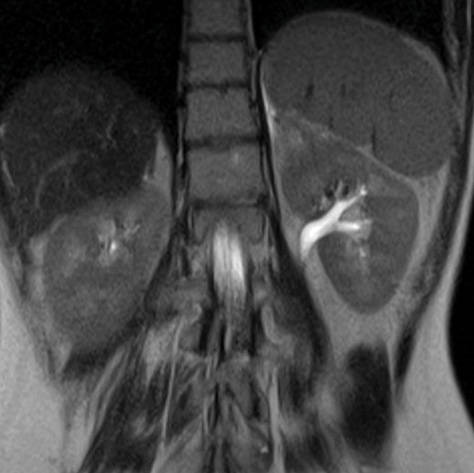

A thoracoabdominal CT scan showed atelectasis of the lower left lung lobe and an oval mass of 5 X 6 cm at the level of the left adrenal gland (Figure 4). Abdominal MRI showed a heterogeneous adrenal lesion, with hyperintense spots due to blood content.

Figure 4. A thoracoabdominal CT scan showing an oval mass of 5 X 6 cm at the level of the left adrenal gland.